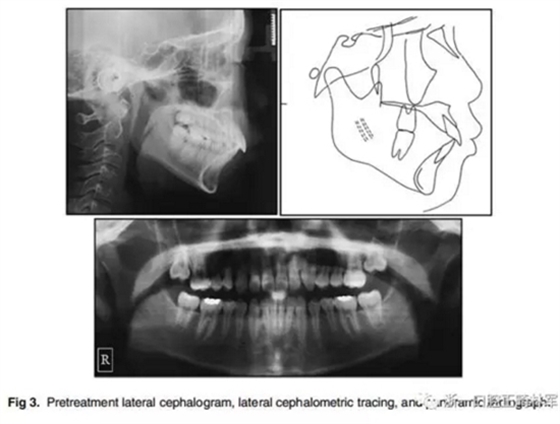

1.口內(nèi)像(Fig 1)、研究模型(Fig 2)和全景X光片(Fig 3)顯示了輕度牙列間隙,覆牙合覆蓋較大,右上第一前磨牙扭轉(zhuǎn)。覆牙合為4.0 mm,覆蓋為5.5 mm,兩側(cè)有輕微的Ⅱ類磨牙關(guān)系。除了上頜第二磨牙以外的所有牙齒都已經(jīng)萌出,患者口腔衛(wèi)生不良,有廣泛的牙齦炎癥,但牙槽骨未吸收。顳下頜關(guān)節(jié)形態(tài)良好,沒有癥狀。

2.在面部照片(Fig 1)中,患者嘴唇嚴(yán)重前突。治療前的側(cè)位X線片(Fig 3,Table)顯示ANB角較大(7.6°),上頜骨突出(A至N距離5.8 mm)和下頜骨后縮(Pog至N垂直距離,-5.6 mm)。上下頜中切牙唇傾(U1 to FH,122.2°,IMPA,106.2°)。美國正畸學(xué)指標(biāo)差異指數(shù)評(píng)分為30分?;颊呒捌涓改敢庾R(shí)到他的下頜骨比上頜骨小得多,他的母親說,由于兒子身材矮小,他很快就開始接受生長激素(GH)治療。他的身高是154厘米,遠(yuǎn)低于他那個(gè)年齡的平均水平,位于倒數(shù)的的10%。